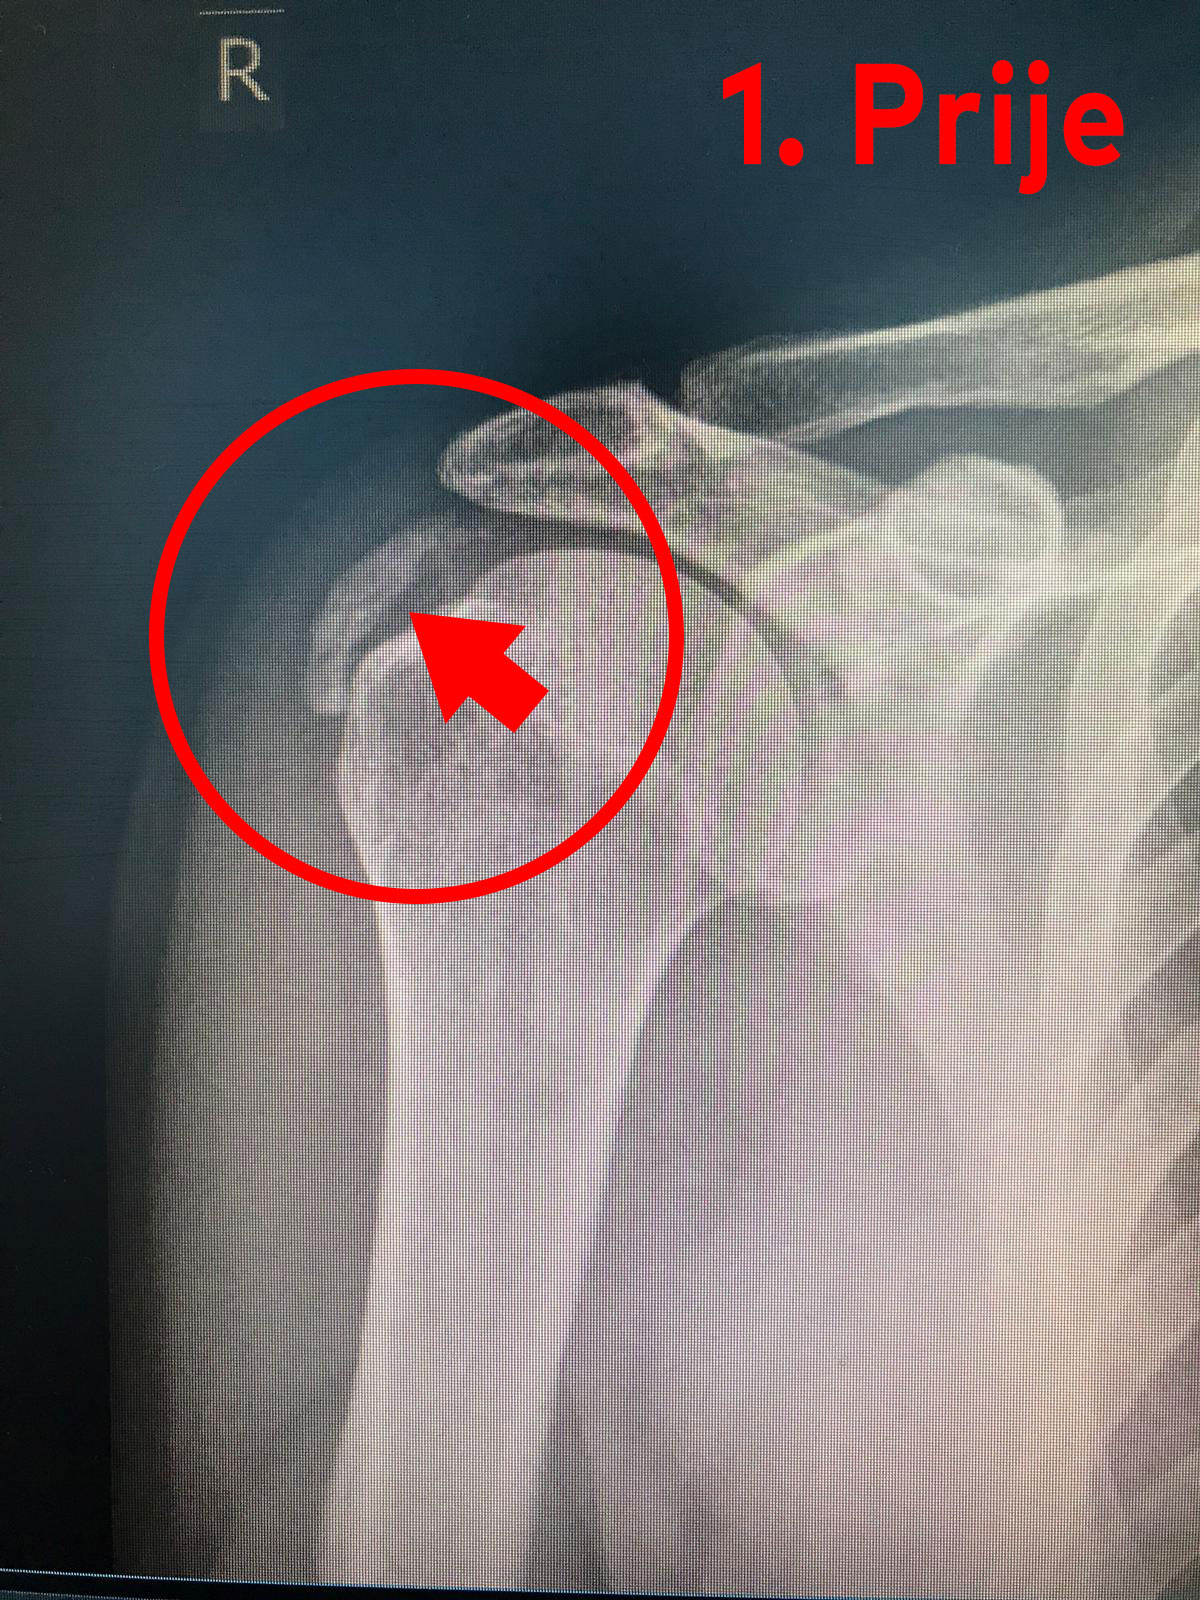

Na slici broj 1 prikazan je slučaj kalcifikata u ramenu prije dolaska na terapiju. Dok je na slici broj 2 prikazan rezultat naše uspješno provedene fizikalne terapije.

KALCIFICIRAJUĆI TENDINITIS RAMENA – odnosno kamenac ili kalcifikat ramena.

Postoji puno uzroka koji dovode do boli u ramenu, a jedan od najčešćih je kalcifikat u tetivama ramenog zgloba – i to u tetivama rotatorne manšete, a posebno je čest u tetivi m. supraspinatus.

Kalcifikat se taloži u dijelu tetive koji je slabije prokrvljen (u tetivi m. supraspinatus oko 1 cm od hvatišta tetive za kost) .